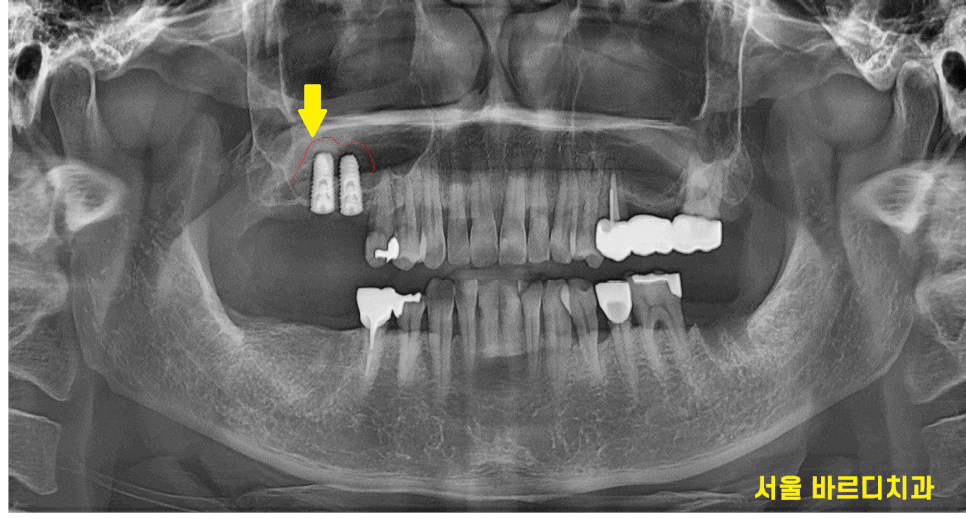

ct를 확인하면 미사 임플란트 시 이식된 뼈이식

확인이 가능하죠~